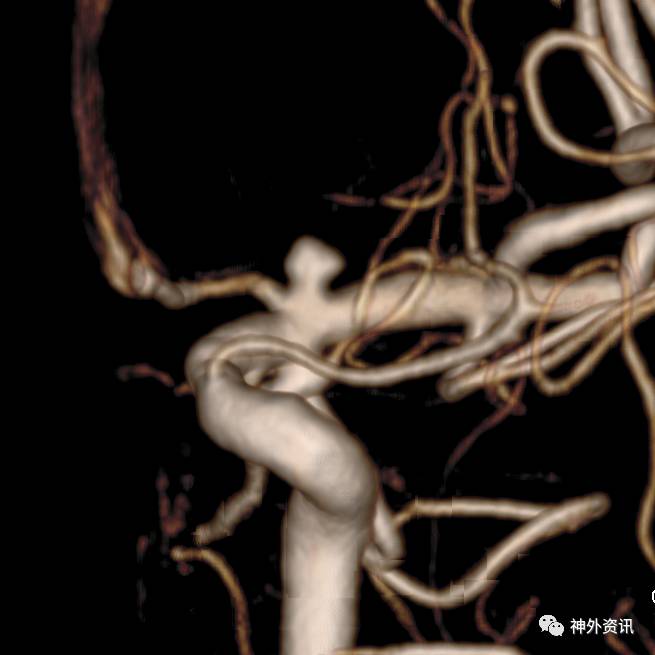

复合立体塑形

塑形考虑血管走行,但是血管内径过大(约>3mm,例如颈内动脉)的情况下,微导管在血管内是螺旋前进(2维是折线前进),即使顺行也需要考虑改变角度。

非同一平面内的弯曲: